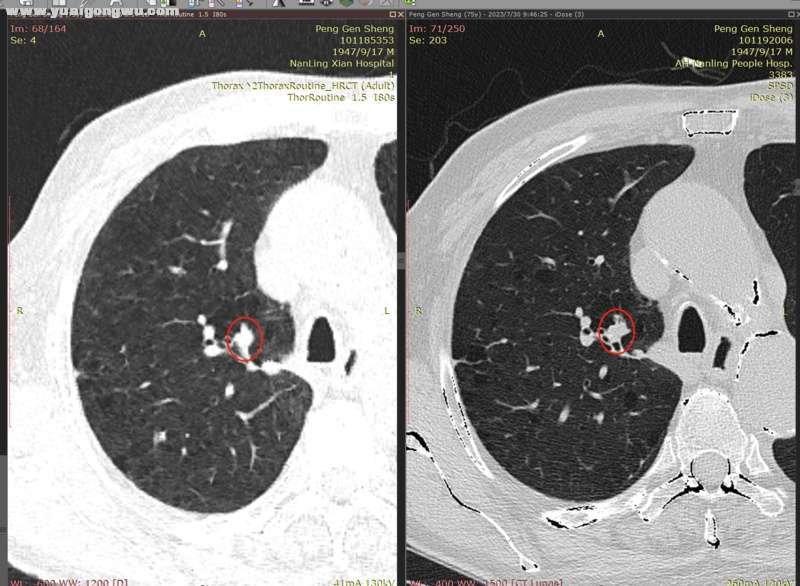

6月3日~7月29日,单用安罗替尼12mg(3周期),6月18日CT显示左肺主病灶稍缩(主病灶62mmx57mm);因近期有一点点吸不上气的感觉(吸氧后有缓解,其他身体体征正常,体感良好),7月30日CT显示左肺主病灶稍增大(主病灶68mmx62mm)。- L* L' w9 C: J7 b

影像科医生将7月30日的胸部CT,和6月18日的胸部CT电子影像对比分析如下:

2、右肺多发小结节,前面两枚之前重点关注的结节(有时变大有时变小),这次复查略微变小(图2~5;+ }% G% E$ F0 e  U; {- |' V' B

* R5 w. e) k/ [9 Y( L' s' h* x* n7 d        以下为近两次CT影像的对比分析。7 Z8 B" @7 n7 B# ?+ K" ?( E( {) v